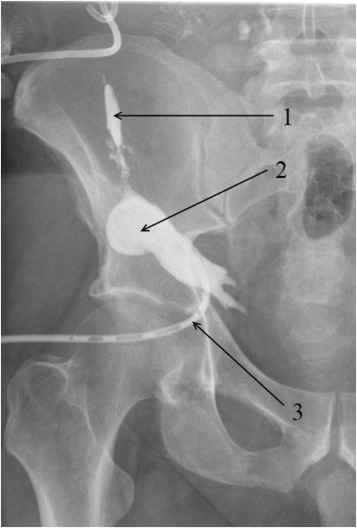

In another case (Patient 22), microfocal pancreonecrosis was complicated by the formation of two sinus tracts, one of which (external) produced an opening on the paraumbilical skin, whereas the second was in the subcutaneous fat in the right iliac fossa, thus forming an abscess (Figure 3).

Subcutaneous fat abscess fistulography: (1) sinus tract leading to the pancreas ...

Subcutaneous fat abscess fistulography: (1) sinus tract leading to the pancreas transplant; (2) abscess cavity in the subcutaneous fat; and (3) drain is in the abscess cavity.

Transcutaneous drainage of the parapancreatic fluid collection and abscess cavity in the subcutaneous fat was performed. Following the fistulography, which failed to establish influx of the contrast into the donor duodenum, closure of all drainage canals was completed by use of a mix of Type 1 human collagen with cancellous bone chips. Asymptomatic parapancreatic fluid collections were observed in 20 patients (50%).